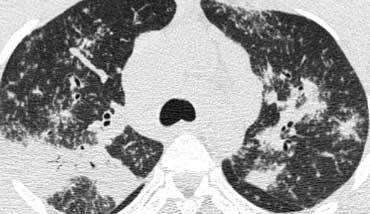

Hình bên trái là bệnh nhân suy giảm miễn dịch mắc PCP.

Hình ảnh CT cho thấy mờ dạng kính mờ lan tỏa.

Hình ảnh này không đặc hiệu cho PCP, nhưng trong bối cảnh lâm sàng này, PCP là chẩn đoán có khả năng cao nhất.

Hình bên trái là một bệnh nhân khác mắc PCP.

Cuộn qua các hình ảnh để xem.